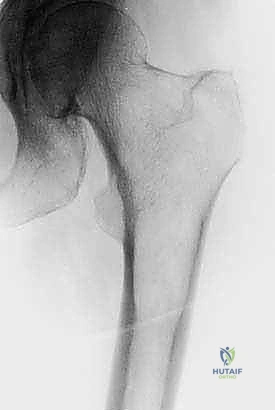

| الأشعة السينية (X-Rays) | الكشف الأولي عن تآكل العظام والكسور الكبيرة. | دقة متوسطة. تُظهر التلف فقط إذا فقد العظم 30-50% من كثافته. |

| عظم الفخذ (القسم العلوي) | كسر عنق الفخذ، العجز عن المشي. | استبدال مفصل الورك بمفصل صناعي (Arthroplasty). |

| جسم عظم الفخذ أو الساق | كسر مرضي كامل أثناء التحميل. | التثبيت بمسمار نخاعي تشابكي (Intramedullary Nailing). |